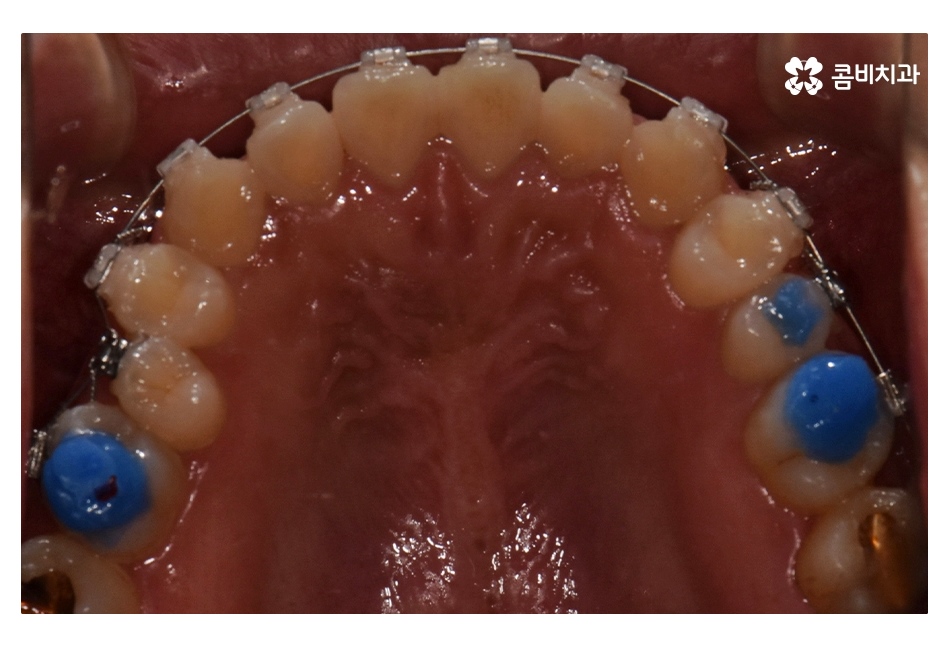

위 환자분의 경우 충치로 인해 오른쪽 아래 제1대구치와

왼쪽아래 제2대구치가 상실된 상태였으며, 치아교정만으로는

치료가 불가능한 케이스였기 때문에 비발치 교정으로

진행하면서 외과수술이 병행된 케이스라고 할 수 있어요

클리피씨교정을 통해서 약 1년 6개월간

치료가 진행이 되었고, 수술과 병행이되며, 치료 마무리 단계에서

임플란트 수술까지 진행이 된 사례라고 볼 수 있는데요.